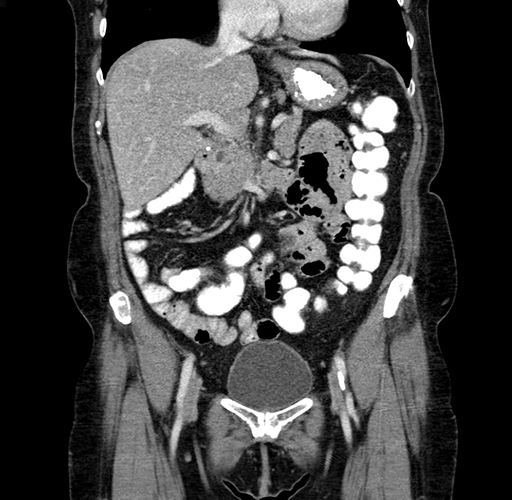

Pre-Chemo: Coronal Venous

Coronal Venous